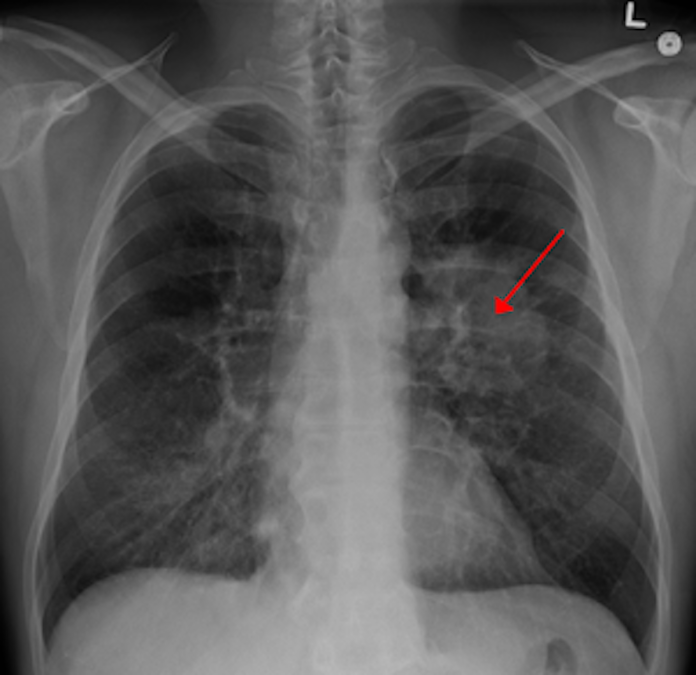

Cancerul pulmonar este cel mai frecvent tip de cancer din România,  cauzează anual cele mai multe decese și cei mai mulți ani de viaţă pierduți prin decese premature. Depistarea din vreme înseamnă opțiuni mai bune de tratament și o calitate mai bună a vieții, spun medicii. Românii întârzie să meargă la medic pentru că nu cunosc simptomele și le e teamă de un diagnostic grav.

Cancerul pulmonar reprezintă creșterea necontrolată a unor celule anormale la nivelul plămânilor. Spre deosebire de celulele normale, celulele canceroase cresc fără ordine sau control, distrugând țesutul pulmonar sănătos din jurul lor. Aceste tipuri de tumori se numesc tumori maligne. Când celulele canceroase se răspândesc, acestea împiedică funcționarea corectă a organelor corpului.